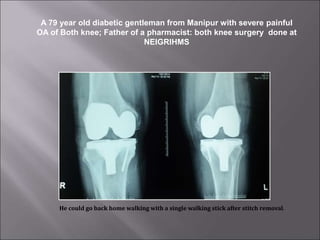

A 79 year old diabetic gentleman from Manipur with severe painful

OA of Both knee; Father of a pharmacist: both knee surgery done at

NEIGRIHMS

He could go back home walking with a single walking stick after stitch removal.